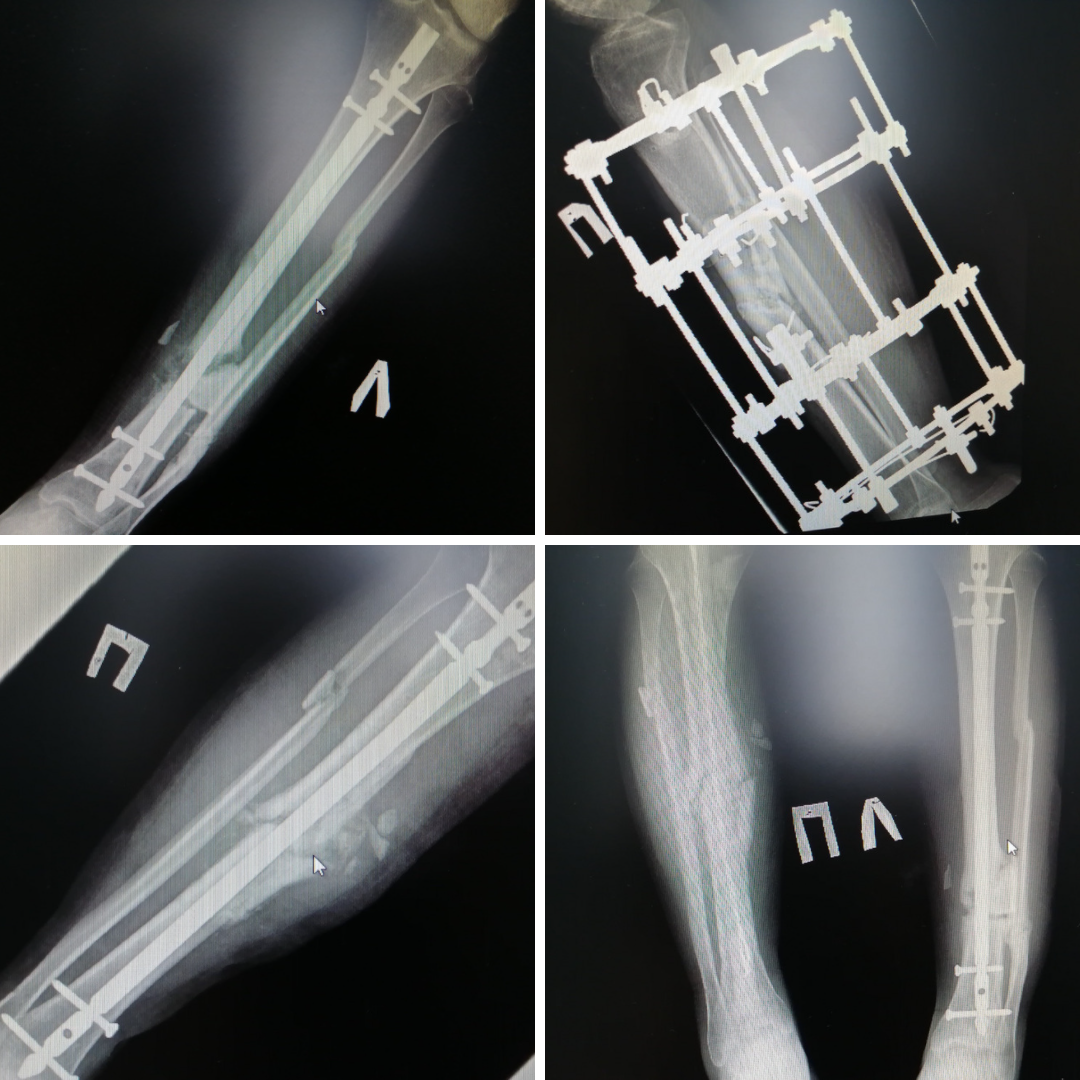

Основные хирургические вмешательства проводил травматолог-ортопед Андрей Миронов. После первой же операции одна нога практически сразу стала опорной. Даже несмотря на то, что сращения ещё не произошло, её можно было постепенно нагружать. Это важно. Без нагрузки кости становятся хрупкими, остеопорозными очень быстро. Выполнен интрамедуллярный, то есть внутрикостный, остеосинтез.

После того, как врачи правильно сопоставили кости, снова был применён метод интрамедуллярного остеосинтеза: в костномозговую полость погрузили штифт и зафиксировали отломки. Однако организм не принял инородное тело и отреагировал воспалительным процессом. Штифт пришлось на время убрать, заменив его антибактериальным спейсером - трубкой со специализированным костным цементом и антибиотиком. Параллельно лечили и соседние ткани, используя современные вакуумные системы. И только когда полностью справились с воспалением, остеосинтез повторили. На этот раз обошлось без нежелательных последствий.

– Сразу было понятно, что при таком запущенном случае на лечение понадобится много времени. Молодой человек провёл у нас несколько месяцев. И после выписки он продолжает постоянно наблюдаться. Уже сейчас пациент с умеренной нагрузкой передвигается на костылях. Мы делаем ставку на способность молодого организма к восстановлению и надеемся на скорейшую консолидацию перелома, – добавляет Евгений Бойко.